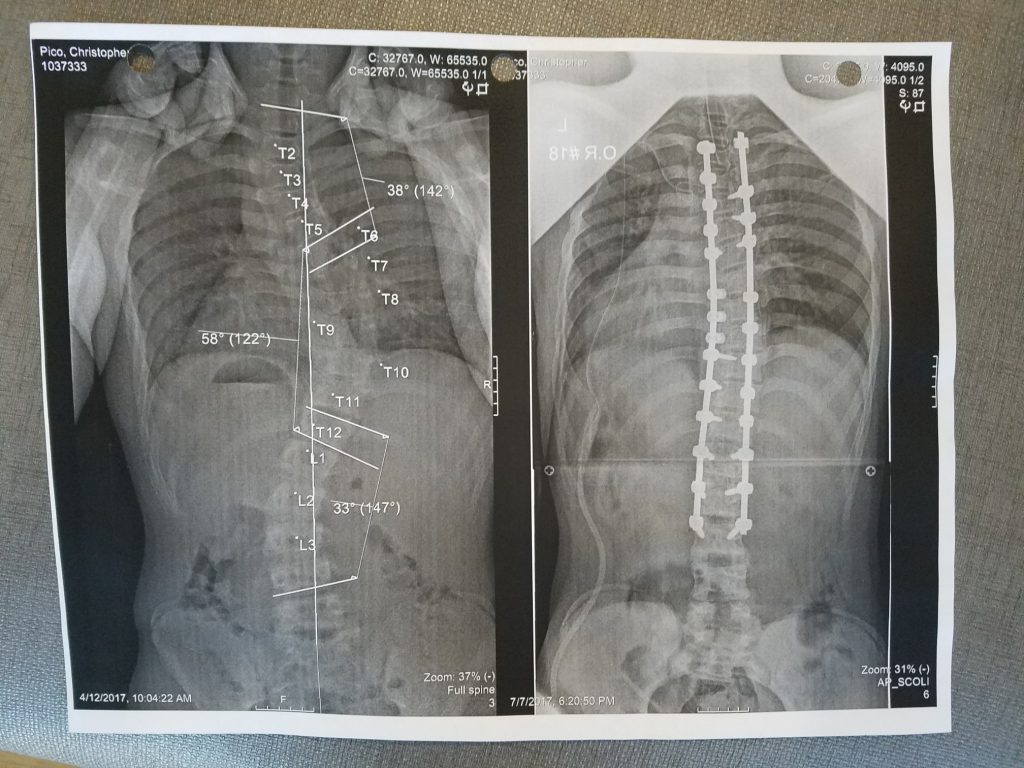

I've been going to HSS for 9 years due to my scoliosis. I had two curves in my spine, one that was as high as 53 degrees. The surgery was a culmination of my time at HSS. Before the time of the surgery I was feeling nervous and concerned, but after reassuring myself about what a great job HSS does I gave them my full faith and trust. After my surgery my pain was managed so well, and the nurses and staff were all great. You can tell that they really do care. I still cannot believe how fast I was making progress with walking, steps, leaving the hospital, and so on. I cannot thank everyone in HSS enough for how much they helped me.